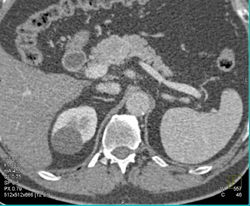

Diagnosis

Intraductal Papillary Mucinous Neoplasm (IPMN)